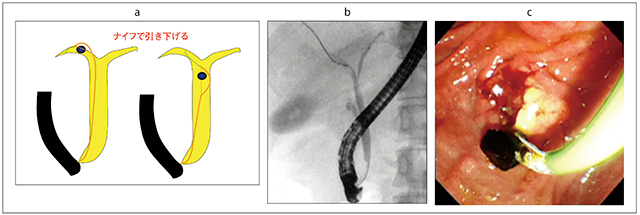

最後に、嵌頓結石について触れたい(図17)。嵌頓結石に対しては、ガイドワイヤ越しに行うことが有用である。ガイドワイヤがうまく奥まで入った場合には、必ず先端チップが細いバスケットあるいはバルーンを用いることで、安全に採石できる(図18)。また、POCSも有用なほか、当科では、レーザーあるいはEHLも実施することが多い。肝内胆管迷入嵌頓結石に対しては、パピロトーム(ナイフ)の刃を振って結石を肝外胆管まで移動させる方法もある(図19)。本症例は、そのままナイフで取り出したが、ナイフから結石を外し、バスケットで採石する方法もある。

図19 パピロトームによる肝内胆管嵌頓気味結石の除去

a:肝内胆管へ迷入した嵌頓結石への対応

b:パピロトームで結石を移動させる

c:乳頭から結石が排出された